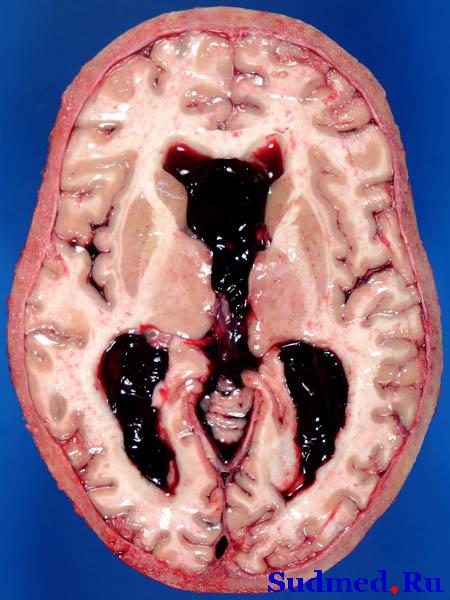

Кровоизлияния и сгустки крови в мозжечках, аневризма a. communicans anterior.

Труп молодого человека 22 лет, был доставлен в секционную из реанимации.

Из истории: ехал в маршрутке, упал в эпиприпадке, скорой был доставлен в реанимацию, в сознание не приходил. В коме был 20 дней. Врачи из реанимации, присутствующие на вскрытии, утверждали, что больной приходил в сознание, и даже активно совершал целенаправленные движения. Но помоему, судя по характеру заболевания, это нонсенс. Также больной залит (отёк мозга, отёки всех внутр. органов, транссудаты в полостях, причём, в правой плевральной полости жидкости до 1,5 л).

Теперь по изображению. Если я правильно понял, и правильно вижу, то это свёртки крови в боковых желудочках. Прошу извинить если я не так вижу, но это опять же проблема фотографа. Хорошая иллюстрация не задаёт вопросы, а отвечает на них. Если Вы хотели показать свёртки в боковых желудочках, то на фото обязательно должен быть срез и стенка видны. Иначе всякие дотошные типа меня лишние вопросы задавать будут.

И главный вопрос. Каким образом располагалась аневризма в области передней коммуникантной артерии если кровь в боковые желудочки прорвалась? Вот это самый интересный морфологический аспект Вашего случая. Я вообще не припомню спонтанно ни одного подобного случая у себя. Обычно в этом регионе аневризмы дают гигантские пластинчатые базальные кровоизлияния. Так что случай крайне редкий и морфологически интересный, не стандартный. Жаль, что Вы лишь рутинно его обработали. Поколдовали бы немного над находками и можно было бы даже стендовое сообщение по случаю сделать. Нам бы радость, а Вам почёт и публикация.

Чтобы не быть голословным выставляю свой похожий случай, но уже двухлетней давности. Если Вы обратите внимание на расположение внутренних сонных артерий, то поймёте почему прорыв в боковые желудочки произошёл.